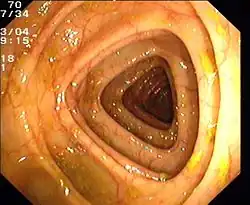

Endoskopische Untersuchung des Colon transversum (Normalbefund).

Der Dickdarm kann mit den Händen und Fingern, endoskopischen und anderen bildgebenden Verfahren untersucht werden.

Zur endoskopischen Untersuchung stehen verschiedene Verfahren zur Verfügung. Das Rektoskop ist ein starres Endoskop, das nur zur Beurteilung von Analkanal und Rektum geeignet ist. Eine Sigmoidoskopie zur Beurteilung des Darms bis zum Colon sigmoideum kann mit einem bis zu 60 cm langen, flexiblen Endoskop erfolgen.[54] Die Koloskopie (Darmspiegelung) ist die endoskopische Untersuchung des gesamten Dickdarms mit einem langen Endoskop. Sie gilt als Goldstandard für die Beurteilung der Schleimhaut. Mit diesem Verfahren können nicht nur sichtbare Veränderungen beschrieben, sondern auch Proben entnommen (biopsiert) und kleine therapeutische Eingriffe durchgeführt werden (beispielsweise die Entfernung eines Polypen).[55]